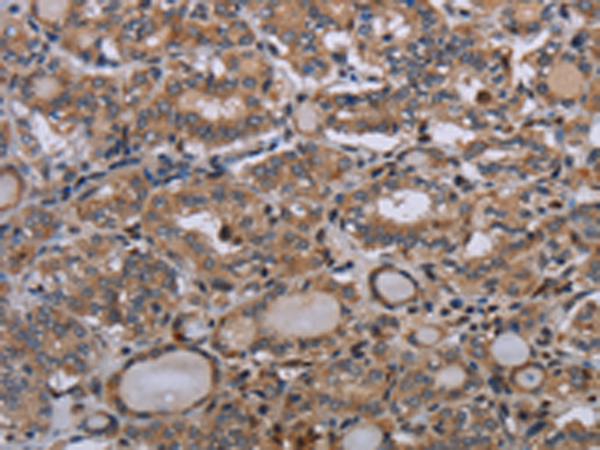

分类: 科研抗体货号: P05048别名: GL004; C2orf33应用: IHC反应种属: Human, Mouse, Rat